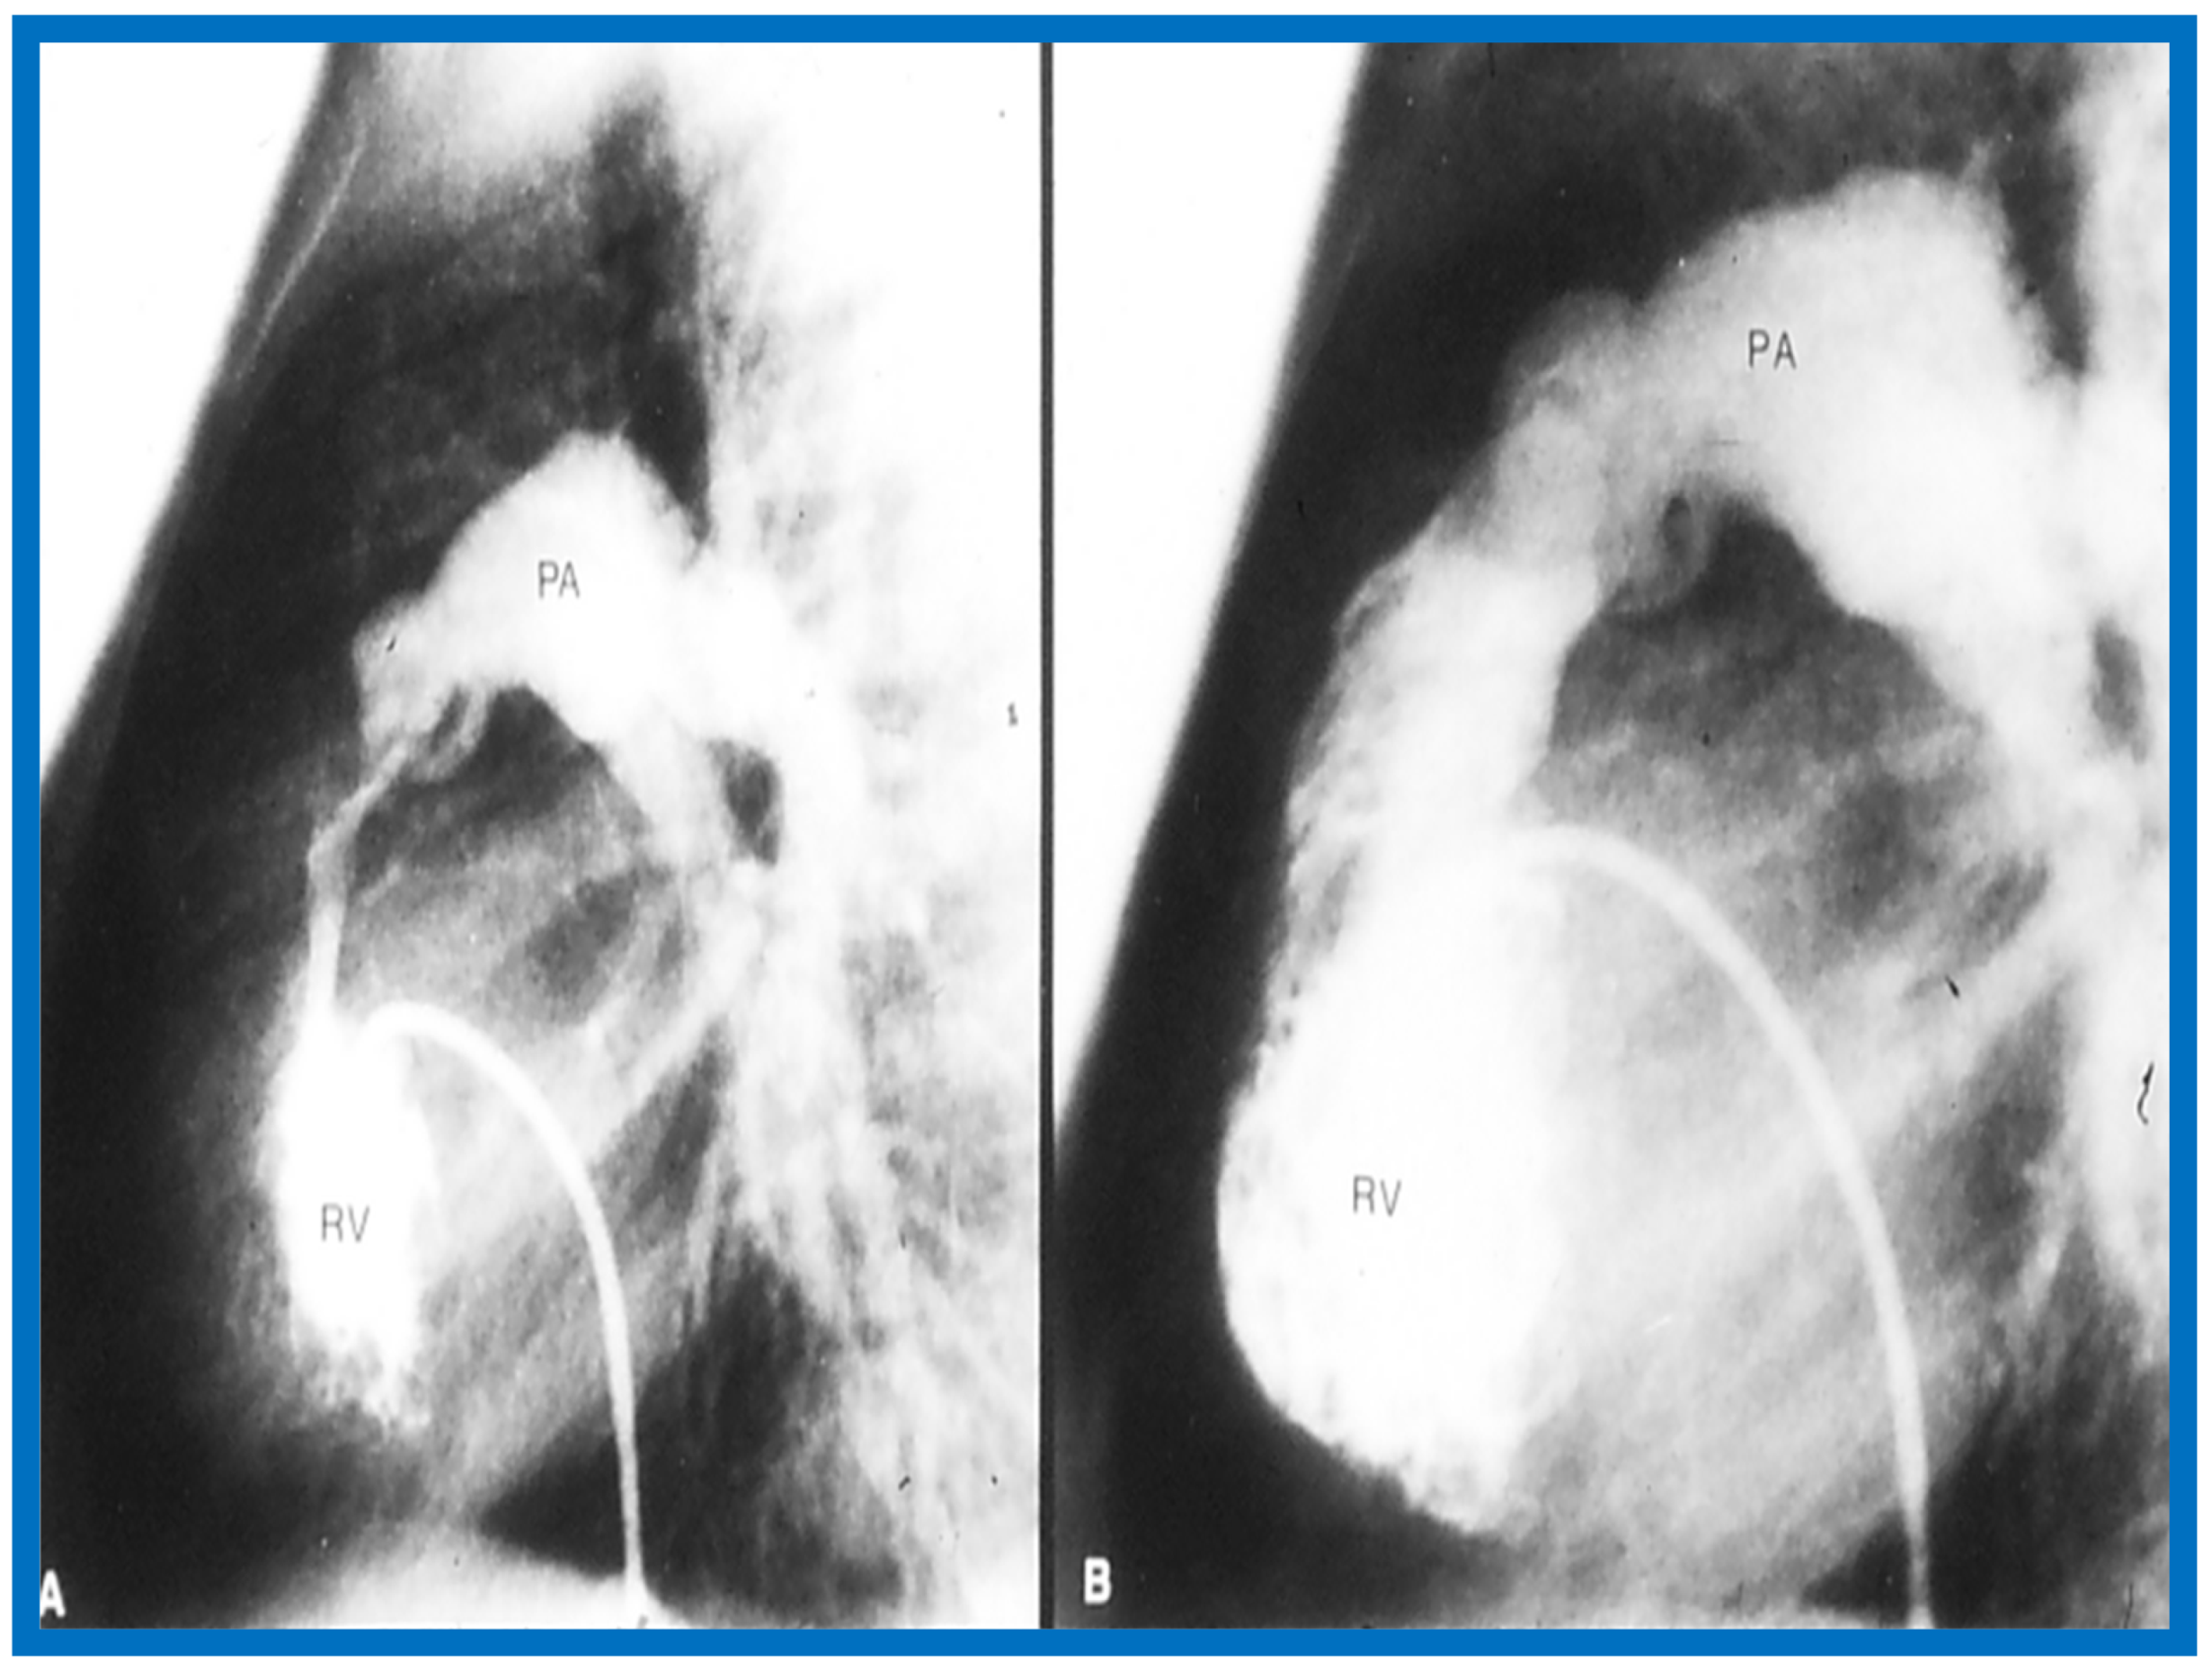

The relationship of Doppler with catheterization-measured pulmonary valve pressure gradients was studied by examining 35 pairs of such measurements, made within 24 h of each other [14]. The correlation coefficient was 0.61 (Figure 46); this improved to 0.91 (Figure 47) after removal of the five patients with severe stenosis (gradients of 94 to 190 mmHg) and one patient with severe infundibular stenosis (Figure 48 and Figure 49).

Figure 48.

Selected right ventricular (RV) cineangiographic frames from lateral projection demonstrating severe infundibular constriction immediately following balloon pulmonary valvuloplasty (A) which has resolved (B) during a study six months later. PA, pulmonary artery. Reproduced from Rao P.S. [14].